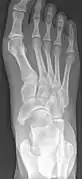

Cornuate navicular bone